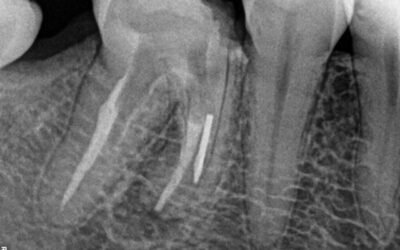

Remoção de Lima fraturada

Existem várias técnicas para remoção de lima fraturada e instrumentos fraturados no canal e é bom que o Endodontista conheça todas elas, pois a cada caso uma determinada técnica pode funcionar em detrimento das outras. Remoção de Lima Fraturada...